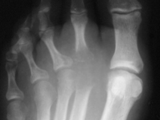

Psoriasis-Foot

Psoriasis-Foot